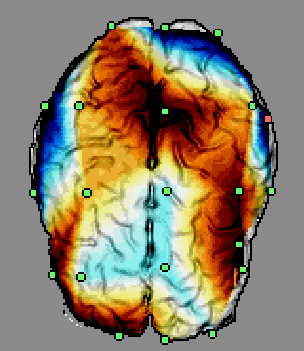

Figure 4. The user interface of 3DEEG software. Several projection planes can be selected.

The measured EEG signal can also be displayed as a smooth animation. The software is also capable in displaying

cortical EEG distributions.

The 3D-EEG program was developed for 32bit Windows operating systems (Win95, Win98 and WinNT) applying graphical

user interface enabling intuitive and efficient operation. The minimum requirements for the hardware are 16MB of

RAM and 16bit color display with the resolution of 800 X 600 pixels. An example of the program's appearance can

be seen in Fig 4.